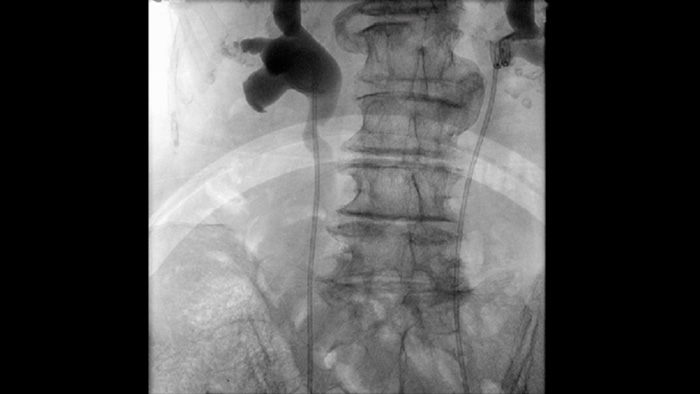

フィリップスの第4世代フラットパネルディテクタシステムにより、消化器科や泌尿器科のさまざまな処置において信頼のある画像を提供します。Unifyワークフローの直観的な設計によりスループットを向上し、ユーザビリティ調査ではイメージ操作時間を短縮できることが実証されています。 Zenition 70には2種類のディテクタサイズがあります。FD26㎝×26㎝は対象部位の視野範囲が広く、コンパクトなFD21㎝×21㎝は患者周囲の狭い部位での使用に適しています。

詳細Philips Zenition モバイルCアームイメージングシステムを使用して、血管の介入や手術中に、より簡単で自信を持って体験してください。